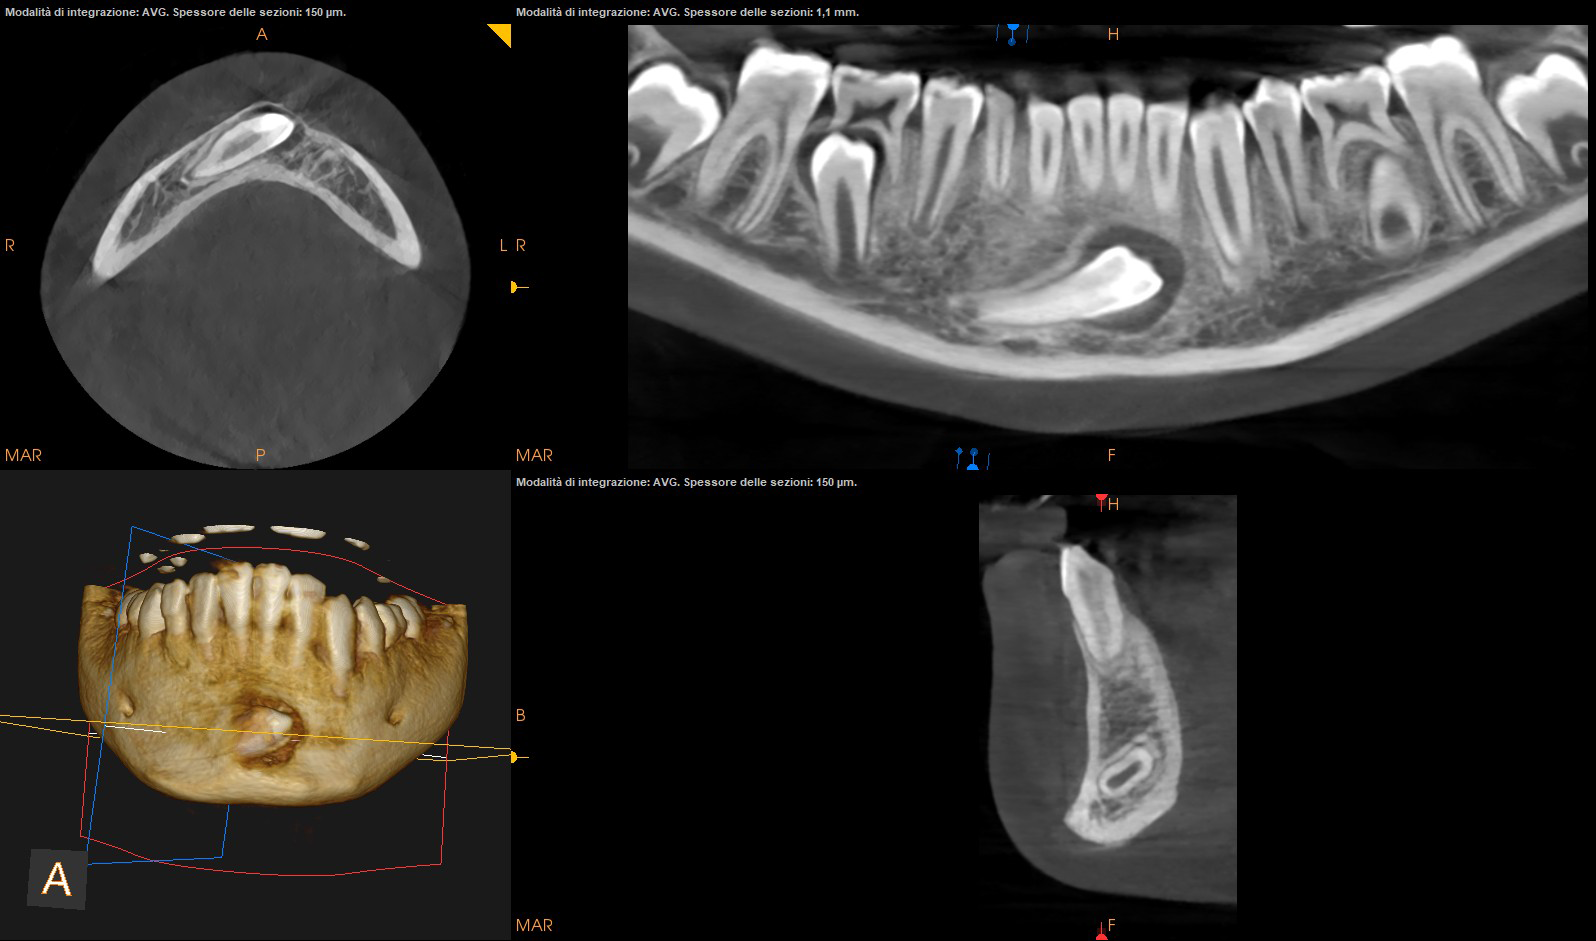

CASO 2

Estrazione di canino incluso in paziente pediatrico

La chirurgia orale nel nostro studio viene affrontata con un approccio d'avanguardia, mirato a garantire la massima precisione nell'estrazione di denti del giudizio e denti inclusi, così come nella rimozione di cisti e lesioni del cavo orale. Per assicurare interventi mini-invasivi, utilizziamo la tecnologia piezoelettrica, che permette di agire selettivamente sui tessuti duri riducendone il trauma e preservando l'integrità delle strutture nobili (nervi e vasi). Ogni procedura è supportata da una rigorosa fase di pianificazione tramite CBCT, che ci consente di previsualizzare l'anatomia in 3D e operare con estrema predicibilità e sicurezza. Di seguito, illustriamo l'approccio clinico applicato a un caso di estrazione di un dente del giudizio e di un canino incluso.Chirurgia Orale